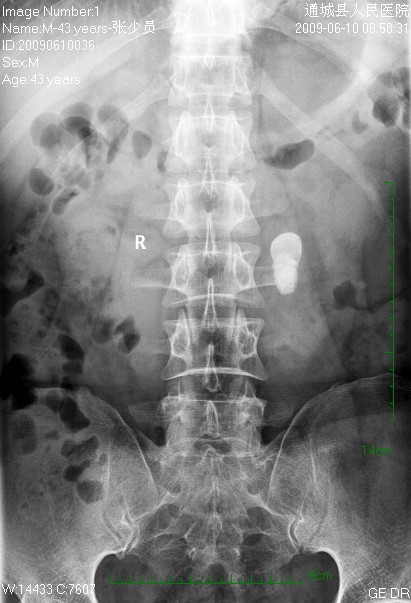

标题: CL1983:尿路结石

左侧输尿管结石并左肾积水